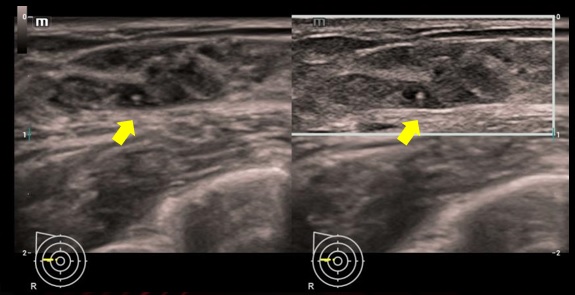

iNeedle - Vylepšenie vizualizácie pomocou ihly iNeedle

iNeedle (kontrastná vizualizácia punkčnej ihly)

iNeedle: Kontrastné zobrazenie bioptickej ihly.

iNeedle: Kontrastné zobrazenie bioptickej ihly.